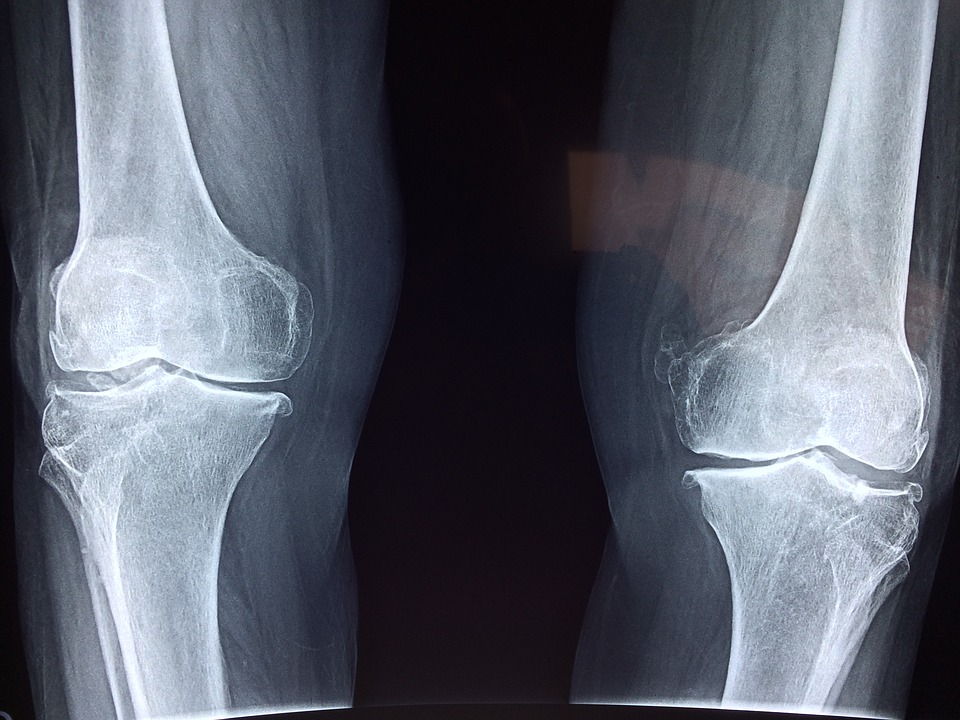

الأشعة

يتم استخدام الأشعة في توضيح شكل التورم حول الرضفة، ويتم استخدام الأشعة السينية من أجل التحقق من عدم وجود خلع أو كسر أو في حالة وجود تاريخ للصدمات ، كما أن الأشعة توضح وجود علامات هشاشة العظام .

التصوير بالرنين المغناطيسي

يساعد التصوير بالرنين المغناطيسي على الكشف عن وجود تشوهات في المفاصل أو عظام الركبة، مثل تمزق الأوتار أو الأربطة، أو الغضروف.